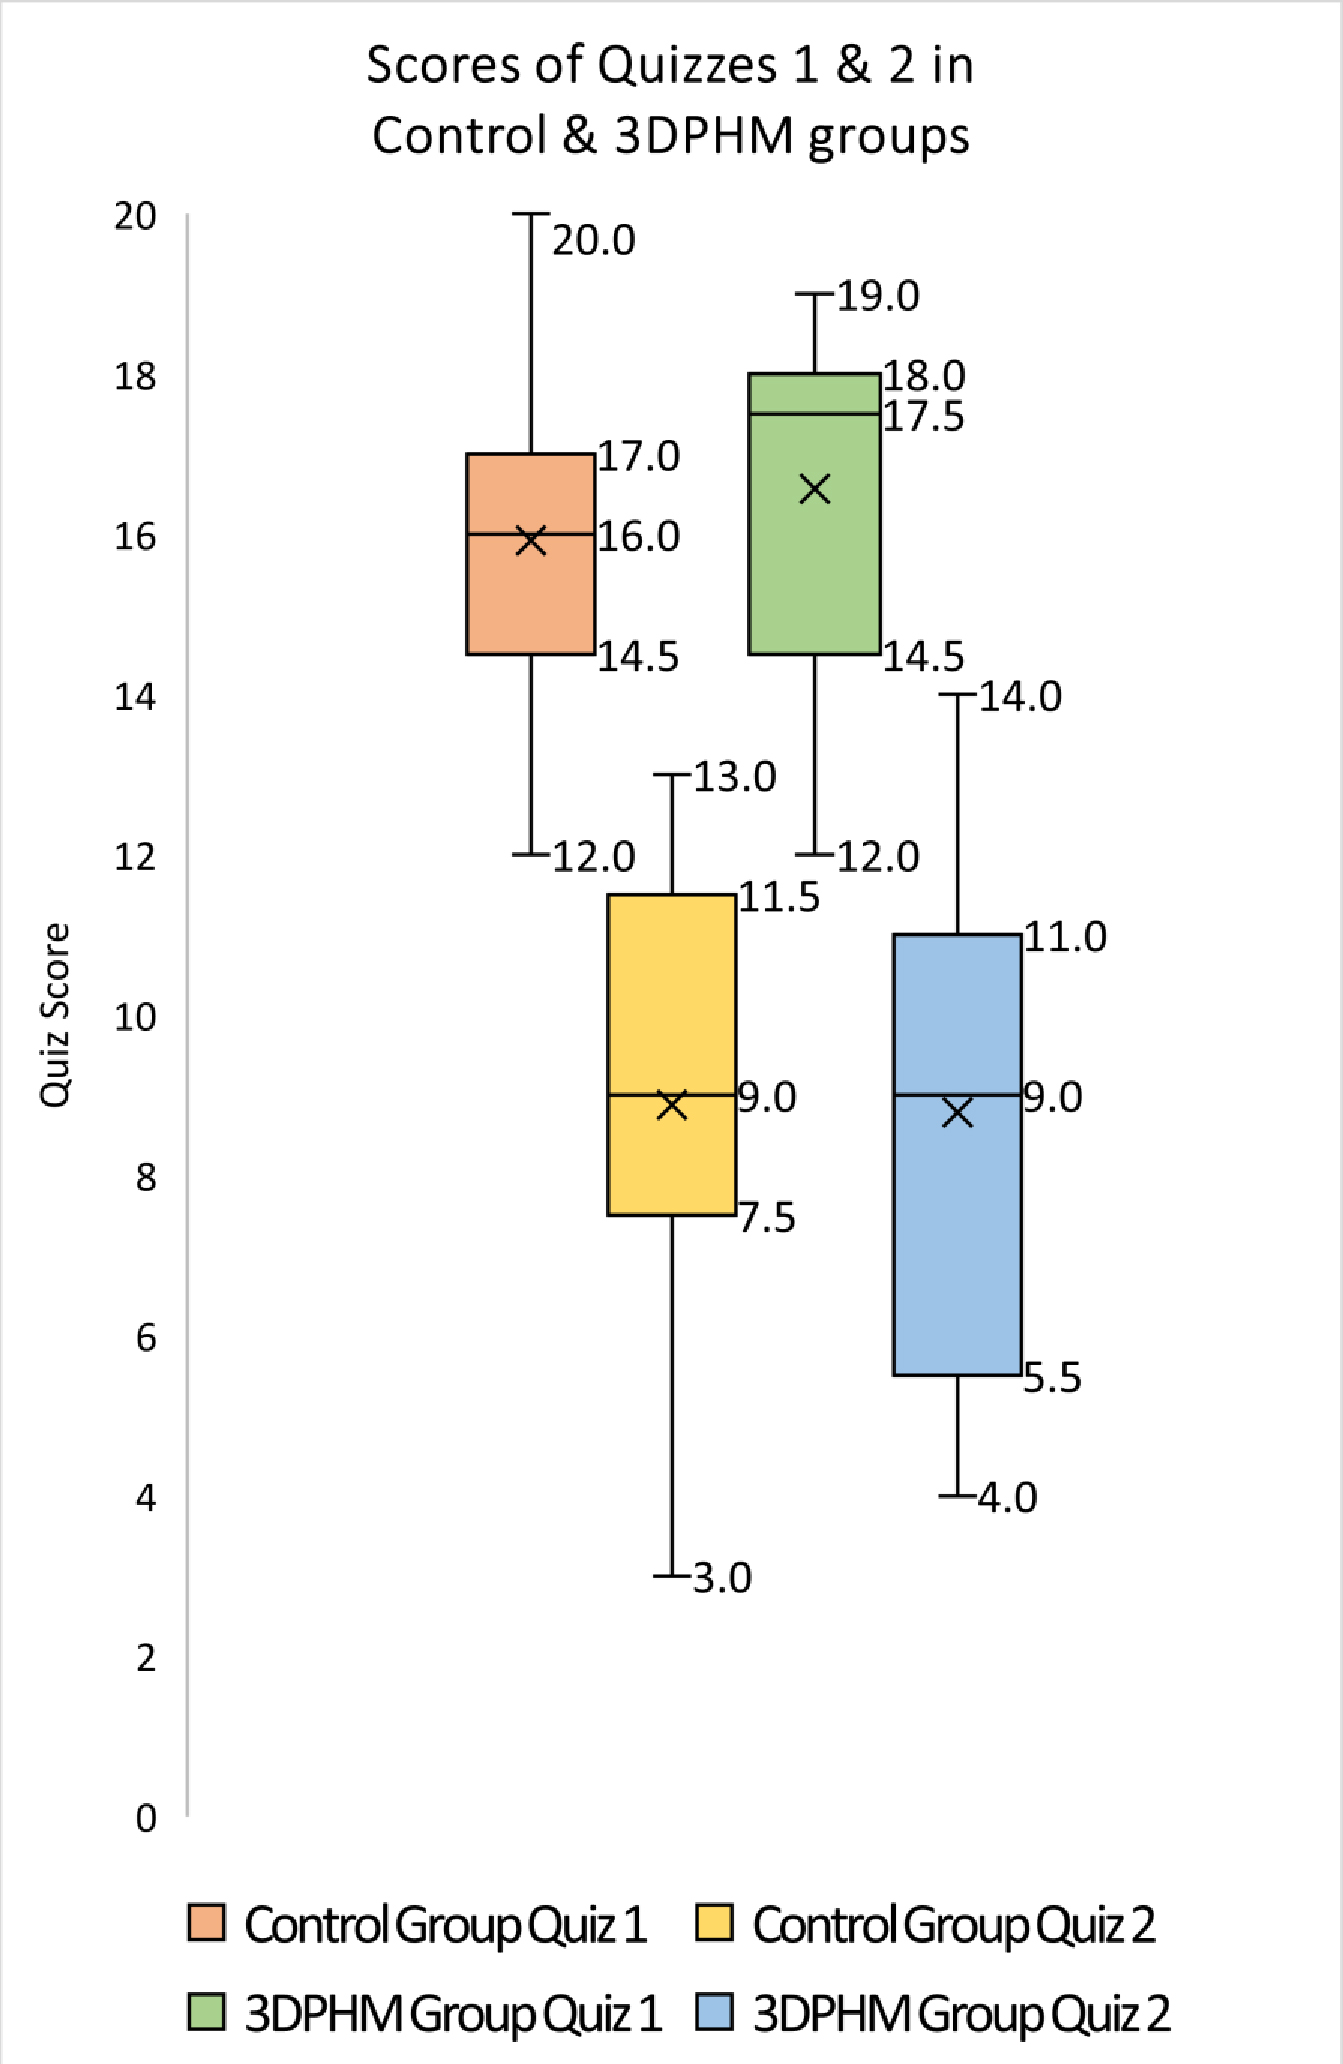

The Quiz 1 score was marginally higher in the 3DPHM group, with a median score of 17.5 and compared to median score of 16 in the control group, however Mann-Whitney U test demonstrates no statistical significance (U = 272, p = 0.16). Fig. 5 presents a boxplot of the scores achieved by both student groups in Quizzes 1 and 2.

Fig. 5.

Fig. 5.Boxplot of the scores (out of 20) achieved by control and 3DPHM groups in Quiz 1 and Quiz 2. 3DPHM, three-dimensional printed heart model.

The 3DPHM group experienced slightly higher score difference between Quiz 1 and

Quiz 2, with a mean score difference of 7.79 (

The results showed that the 3DPHM group scored slightly higher in Quiz 1, which indicated improvement in immediate knowledge acquisition compared to the control group. This difference however, did not achieve statistical significance. This finding echoes the finding in Jones et al.’s [16] study, in which 36 residents were divided into 3D printed model group and control group with their pre-test and post-test scores analyzed. In their study, the 3D printed model group experienced slightly greater improvement in the post-test compared to the control group, however the difference was not statistically significant [16]. In another study conducted by Loke et al. [2], the 3DPHM group did not show improvement in the immediate knowledge gain among the pediatric residents. Despite these positive reports, there are other studies documenting contrasting findings. In a study which involved 63 medical students, the 3DPHM group was reported to have a significant improvement in the test results when compared to the control group [17]. In another study by Lim et al. [7], 53 first year medical students were randomly assigned into three groups (cadaveric materials, 3DPHM, and combined materials) and were objectively tested in pre- and post-test for their knowledge acquisition on external cardiac anatomy. It was reported that the 3DPHM group had significant improvement in test scores (p = 0.003) [7]. This is not a surprising finding. In a meta-analysis conducted by Yammine et al. [18], physical models were reported to significantly improve the overall knowledge outcome and the spatial knowledge acquisition, but not the factual knowledge acquisition. In the present study, we focused on the topic of CHD using 3DPHM which feature 4 different types of CHD. Even though the result did not reach statistical significance, which likely was due to the small sample size, the role of 3DPHM in improving short-term knowledge gain on CHD should not be overlooked, as the effect of 3DPHM on immediate knowledge acquisition appears to vary with the complexity of the CHD. In the study by White et al. [19], residents were objectively tested on two types of CHD of different complexities to explore the usefulness of 3DPHM in improving residents’ knowledge on VSD and ToF. They were divided into 3DPHM and control groups for both VSD and ToF lecture. It was reported that the 3DPHM group scored higher in the ToF post-test (p = 0.037), but lower in the VSD post-test (p = 0.02) [19]. Similarly, in another study by Smerling et al. [3], first year medical students were subjectively tested to assess their perceived knowledge acquisition using 3DPHM of different lesion complexity. It was reported that with the use of 3DPHM, as the complexity of CHD increases, the mean knowledge also increases [3]. This however, was not validated in our study, which could contribute to the findings of no significant difference. This limitation could be addressed in future studies.

Surprisingly, the 3DPHM group performed slightly inferior to the control group for long-term knowledge retention, even though this was not statistically significant. This is in contrast to another study by Lombardi et al., in which plastic heart models were compared to organ dissection of a sheep heart and virtual dissection using physiology software program, to assess the students’ immediate knowledge acquisition and long-term knowledge retention on normal heart anatomy and physiology. It was found that the plastic model group performed significantly better during the initial exam and the 2-month follow-up exam [20]. This difference in findings might be due to the difference in methods of lecture being carried out in both studies. In Lombardi et al.’s [20] study, the students in plastic model group were allowed 45-minute of hands-on activity with the models as well as within-group discussions after 15-minute of PowerPoint lecture; whereas in our study, the students in the 3DPHM group learned individually and had full 1.5 hour of PowerPoint lecture with different teaching tools incorporated throughout the sessions. The amount of time that they spent on the models might not be enough. On the other hand, the study by Lombardi et al. [20] only focused on normal heart anatomy and physiology, whereas our study focused on CHD, which could justify the difference in findings.